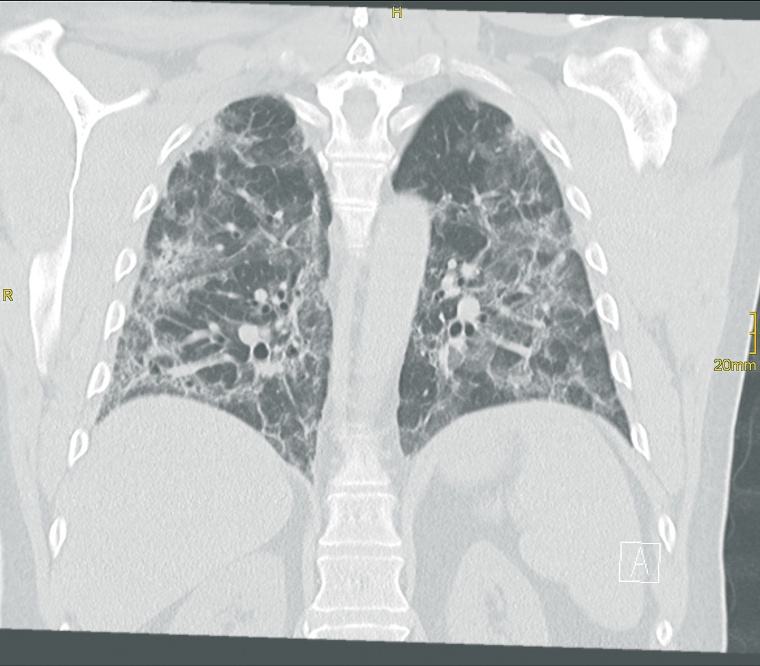

Prof. Dr. Stephan Kloska: Durch unsere sehr aktive Notaufnahme haben wir einen großen Anteil an Patienten mit eingeschränkter Mobilität und nachts ist manchmal nur eine MTRA im Einsatz. Darum brauchen wir ein System, bei dem die Patienten einfach und auch von einer Person alleine umgelagert werden können. Da kommt uns die Funktionalität des Adora-Systems, bei dem keine Umlagerung in der 2. Ebene erforderlich ist, sehr entgegen. In der ersten Pandemiewelle wurden rund 50 % der COVID-19-Fälle der Region im Klinikum Fürth behandelt, in Hochzeiten waren es bis zu 90 stationäre Patienten. Gerade in dieser Phase, wo der Andrang mit Patienten auf COVID-Verdacht ausgesprochen groß war und ist und wir schnell nach COVID-Patienten und Verdachtsfällen vorsortieren mussten, konnten wir mit dem Adora-System in der Notaufnahme sehr schnell agieren.

Kloska: Grundsätzlich kann man sagen, dass es die Überlegungen, auf ein volldigitales System umzusteigen, schon länger gab. Aber Corona hat die Anschaffung noch einmal maßgeblich beschleunigt.

Bayer: Bei einem roboterbasierten System ist eine perfekte Ausrichtung der Strahlenquelle zum Detektor möglich. Dadurch ist es deutlich einfacher, eine optimale Bildqualität bei hoher Dosisreduktion zu erzielen.

Kloska: … was natürlich von den Einstellungen abhängt, da mussten wir noch etwas nachjustieren. Wir haben die Positionierung verändert und die Messkammern umgestellt und die MTRAs mussten eine etwas andere Vorgehensweise wählen. Die Parameter der Canon-Bildverarbeitung wurden letztlich so eingestellt, dass Bildeindruck und Dosisreduktion unseren hohen Anforderungen entsprechen.